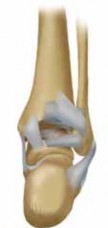

1. The ankle is a modified hinge joint, which relies on a con-gruently reduced mortise to provide optimal function.

5. The anatomy of the distal tibia and ankle joint must be taken into account when considering ankle fractures. As the tibial shaft flares in the supramalleolar region, the dense cortical bone changes to metaphyseal cancellous bone (

8. The medial end of the tibia is the medial malleolus.

1. The medial malleolus is composed of the anterior and posterior colliculi, separated by the intercollicular groove (

FIG 1B

).

2. The anterior colliculus is the narrower and most distal portion of the medial malleolus and serves as the origin of the superficial deltoid ligaments.

3. The intercollicular groove and the posterior colliculus, which is broader than the anterior colliculus, provide the origin of the deep deltoid ligaments.

4. The insertions of the deltoid ligaments (medial tubercle of the talus, navicular tuberosity, and sustentaculum tali) can also be considered part of the medial malleolar osteoliga-mentous complex.

9. The lateral malleolus is the distal end of the fibula. It extends about 1 cm distal and posterior compared to the medial malleolus.

10. The syndesmotic ligament complex unites the distal fibula with the distal tibia. The following ligaments make up the syndesmotic complex: the anteroinferior tibiofibular ligament, the posteroinferior tibiofibular ligament, the inferior transverse ligament, and the interosseous ligament (

FIG 1C

Anterior colliculus

Talonavicular ligament

Superficial deltoid ligament

Tibia

Fibula

Tibiotalar joint Talus

Posterior colliculus

Deep deltoid ligament

A B

Interosseous membrane

Anteroinferior tibiofibular ligament

C

Transverse ligament

Posteroinferior tibiofibular ligament

Posterior talofibular ligament

Calcaneofibular ligament

FIG 1 • A. Bony anatomy in the supramalleolar region of the distal tibia. B. Anatomy of the medial aspect of the ankle joint. C. Ligamentous anatomy about the ankle joint. careful neurosensory examination must be documented prior to manipulation. IMAGING AND OTHER DIAGNOSTIC STUDIES 1. Radiographic examination includes the ankle trauma series: anteroposterior (AP), lateral, and mortise view (FIG 3A–C).